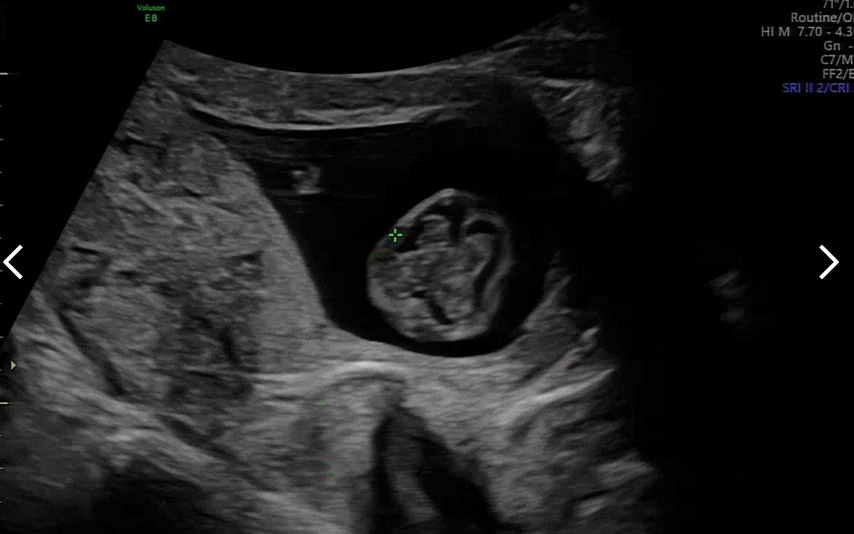

뇌도 예쁜 나비 모양으로 잘 형성되고 있다고 하셨다. 너무 신기하다.

다리도 길쭉하게 뻗어가고 있고 손, 발 모두 잘 형성되고 있다. 2차 정말 검사에서는 손가락, 발가락 갯수도 정확히 볼 수 있다고 하셨다.